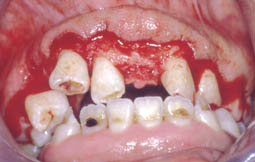

- L’examen du parodonte superficiel montre une hypertrophie généralisée recouvrant presque la totalité des dents.

La gencive est de type fibreux avec des foyers œdémateux notamment en regard de la 12 et la 13, et au niveau du groupe incisivo-canin inférieur du fait de l’accumulation de la plaque plus accentuée à ces niveaux (Fig.1 et 2).

- L’examen du parodonte profond met en évidence la présence de fausses poches allant jusqu’à 6-7 mm (Fig. 3),